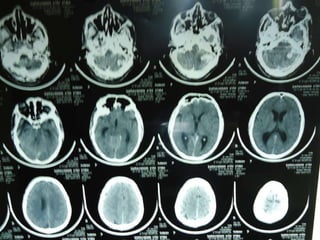

41 yr old saravanan was admitted with  c/o vomiting 1 episode,altered sensorium and difficulty in walking since morning.no h/o of trauma  Not a k/c DM ,SHT. Not a smoker/alcoholic o/e irritable nystagmus+,pooling of saliva+,9 th  and 10 th  N palsy,b/l plantar withdrawal BP-120/80mm Hg

Investigations  Echo normal Coagulation profile normal Homocysteine level slight increase

Imaging: AV Malformation